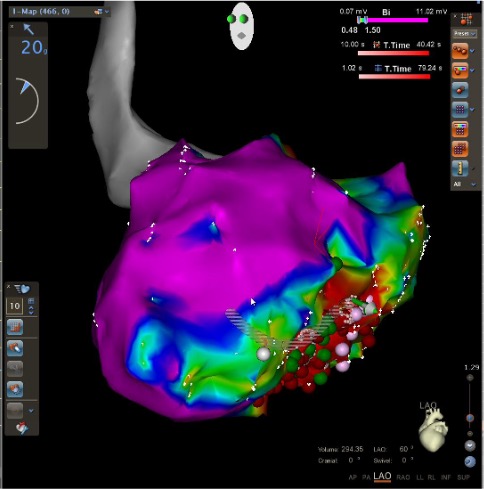

Patients with life-threatening fast heartbeats originating from the ventricles.